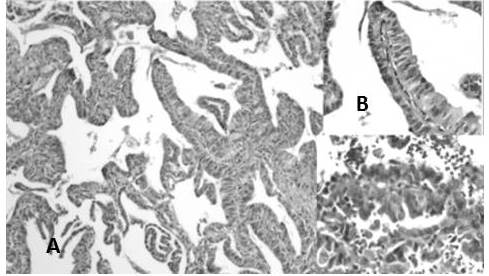

En la reclasificación los casos de ADC estuvieron representados por: ADC patrón predominantemente sólido 57,3 % (Figura 3 y 4), ADC patrón acinar 18,2 % (Figura 5) y en menor frecuencia ADC con patrones mixtos como: patrón predominantemente sólido y acinar 3,6 %, ADC patrón predominante sólido con células en anillo de sello 2,7 %, ADC patrón predominante acinar y micropapilar (Figura 6), patrón predominantemente acinar y sólido, papilar y acinar y patrón predominantemente papilar (Figura 7) cada uno con 1,8 %, asimismo, se encontraron en menor cantidad los siguientes patrones: lepídico no mucinoso (Figura 8) tipo intestinal (Figura 9), mucinoso (Figura 10), y otros patrones mixtos con 0,9 % cada uno (Cuadro 4)

Al relacionar los casos de ADC clasificados según lo establecido por la OMS 2004 y reclasificados según OMS 2015 encontramos que los casos con diagnóstico de ADC bien diferenciado se reclasificaron en ADC patrón predominante papilar y acinar con 1,8 % de los casos cada uno; los ADC moderadamente diferenciados fueron reclasificados en ADC patrón predominantemente sólido 21,8 % y acinar 18,18 % aunque se observó un caso de ADC tipo intestinal; los ADC antes clasificados en poco diferenciados se reclasificaron en patrón sólido en la mayoría de los casos 32,0 %; los casos de ADC previamente clasificados como bronquiolo-alveolares se clasificaron en patrón lepídico, papilar y micropapilar (50 % del componente micropapilar), un caso clasificado como sugestivo de ADC que resultó en ADC sólido; por otra parte casos previamente clasificados como CCE fueron clasificados como ADC patrón sólido (11,81 %) aunque se observó un caso con el diagnóstico de patrón acinar (Cuadro 5)